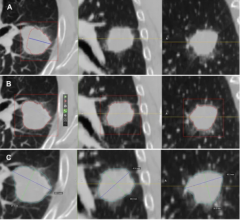

March 21, 2019 — Using data from computed tomography (CT) images, researchers may be able to predict which lung cancer ...